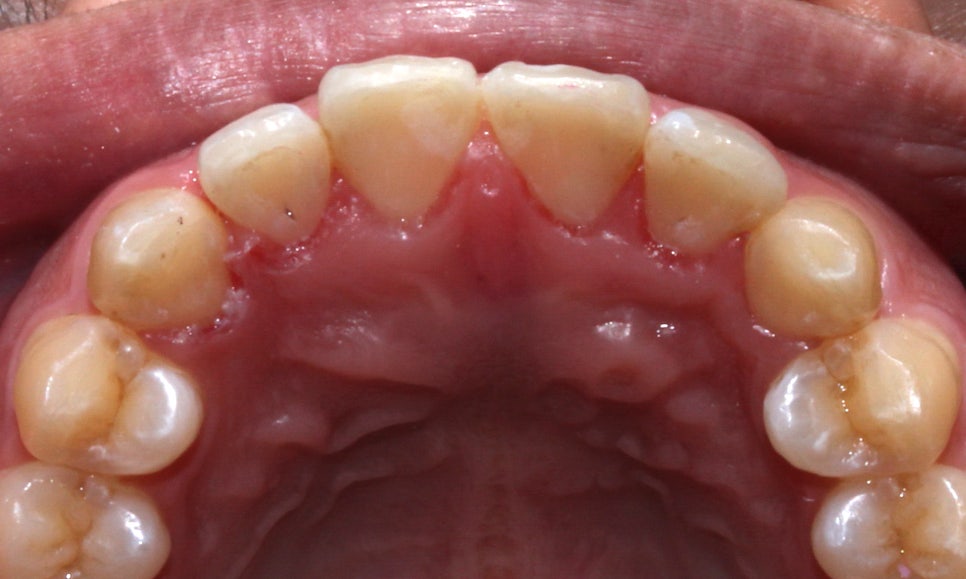

앞니의 경우 뻐드러짐이 심해서

바깥 방향으로 치아들이 누워있는 모양인데요,

아랫니는 치열이 고르지 못하고

들쭉날쭉하게 배열되어 있어

이를 교정하기 위해 2D교정을 시작했습니다!

앞니가 입술 방향으로 뻐드러져 있었던

교정 전 윗니와 달리 교정 후

치열이 가지런해지고 돌출감도 사라진 모습이에요^^

총생으로 들쭉날쭉하게 배열되었던

아랫니 역시 교정 후 치열이 가지런하고

바르게 교정된 모습입니다!